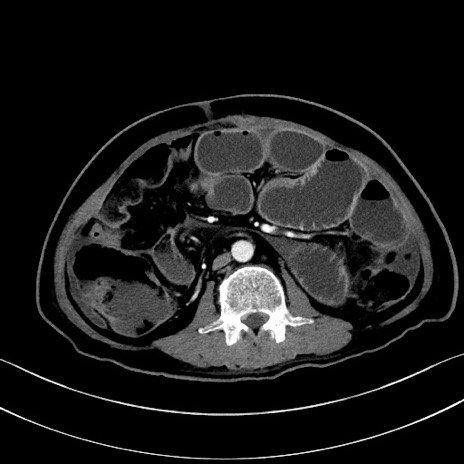

症例28(横断像)

【症例】60歳代男性

【主訴】嘔吐

【現病歴】胃癌にて胃全摘後。食思不振が悪化し、夜中に嘔吐することがある。

【既往歴】胃癌、胃全摘、脾摘、胆摘後

【データ】WBC 5900、CRP 10.56